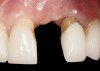

Problem: The implant is placed too facially, and there is significant labial gingival recession, contour change, and mucosal discoloration around the implant, abutment, and crown (Figure 3 and Figure 4). The implant attachment apparatus is intact and healthy, but the patient has a thin periodontal phenotype.

The following case report provides an example of this case scenario: A 28-year-old white female patient presented with her maxillary right lateral incisor significantly longer than the contralateral tooth following restoration of an existing crown that was 10 years old (Figure 3). The patient was dissatisfied with the esthetic appearance of the restoration due to the increased length, recession of the gingival tissues, and discoloration of the surrounding mucosa (Figure 4). Similar to case scenario No. 1, the first step in treatment was to decoronate the healthy implant by placing a flat surgical cover screw and employing a provisional resin-bonded-retained (RBR) prosthesis as a transitional fixed restoration (Figure 5 and Figure 6). The gingival augmentation in situ was allowed to take place for 2 to 3 weeks and was evaluated after that time (Figure 7).

Fig 3. A patient presented with a high smile line and midfacial recession of the maxillary right lateral incisor as evidenced by the increased tooth length compared with the contralateral lateral incisor.

Figure 3

Fig 4. Intraoral view of tooth No. 7 with the gingival zenith more apical than the adjacent central incisor and canine tooth.

Figure 4